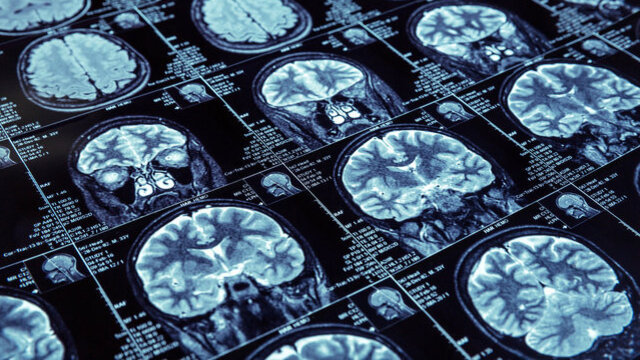

Beyin Sağlığı

Beyin Sağlığı Haberleri